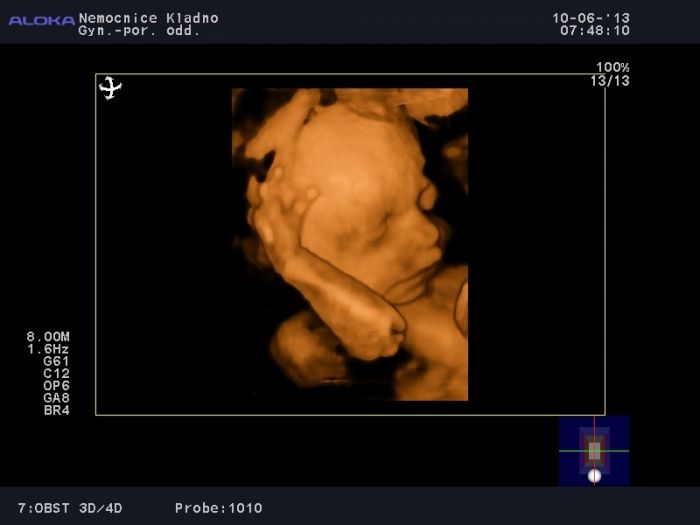

Ráno jsme byli na ultrazvuku na natočení video a nějaké fotečky. Akorát jsme vstávali před 4tou, protože Toko bylo vyspinkané a mě už spát nenechalo. Čekali jsme, že bude odpočívat alespoň při natáčení.. jenže NE. Ale pani asistentka byla úžasná a neuvěřitelně trpělivá a výsledek hodinové práce stojí za to..

[327997] Toko je nádherné!

Opravdu povedená fotečka.

Jinak TOKO je opravdu pekny .. hezkounka fotka ten muj je stydlin takze je videt jen z profilu s rucickou u obliceje a druhou pulkou obliceje nalepeny na placentu

(jinak mi prijde,ze TOKO vypada jako kluk)